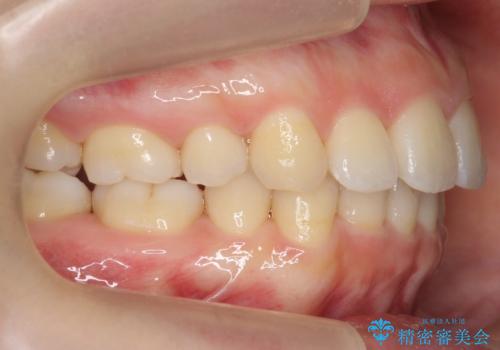

- 小さいころに小臼歯を抜歯しワイヤー矯正をしたが、すき間が空いてきて、前歯の並びが戻ってしまったとのこと。

インビザラインライトという部分矯正コースで、全体矯正に比べ、比較的安価に治療しました。

前歯の並びが格段にきれいになり、大変喜んでいただけました。